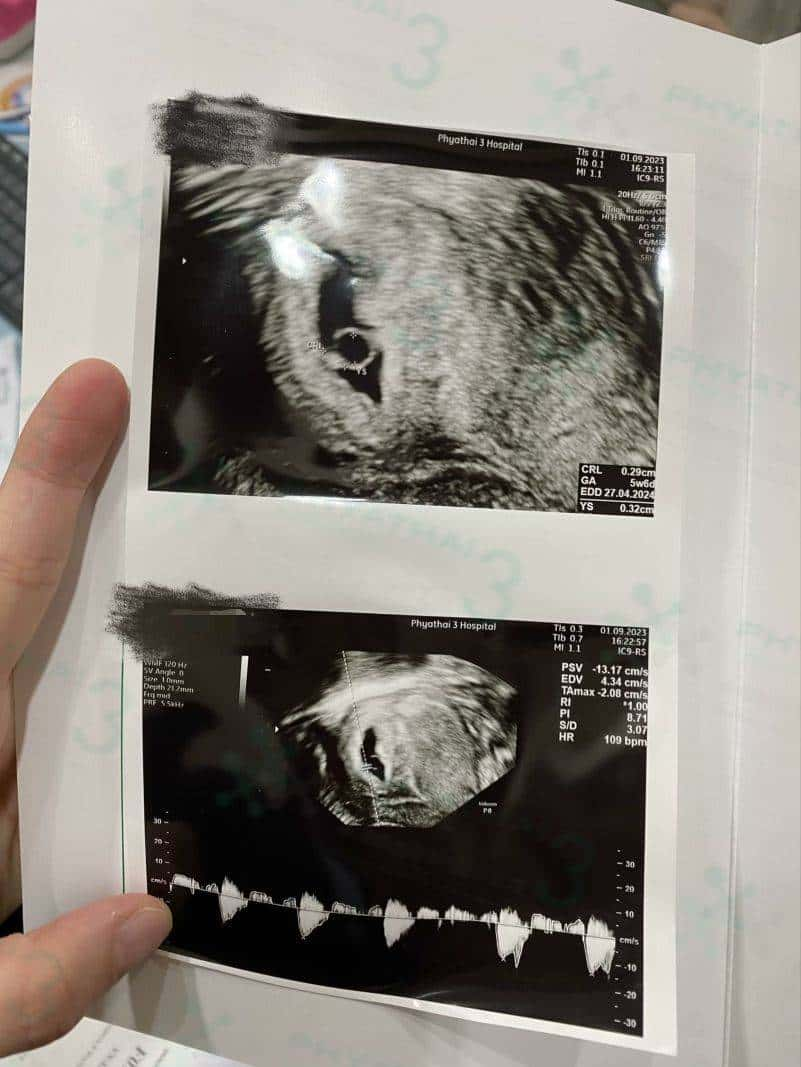

做试管跟自然怀孕,保胎的方式或做产检都是一样的,一般验孕成功之后患者就可以马上回国,后期在国内按照国内医生保胎和定时间做检查。正常情况怀孕6周查孕囊,8周查胎心胎芽,12周左右就可以开始做NT检查。

NT检查比普通B超细致很多,但有可能做检查的时候也会比较长,因为宝宝的每一个器官医生会仔细检查。今天宝宝很配合,医生截图拍照的时候就非常清晰。这被认为是第一次能清楚地看到宝宝的检查。看起来非常激动~希望后期孕妈妈们一切顺利,再等几个月,就能见到宝宝了。